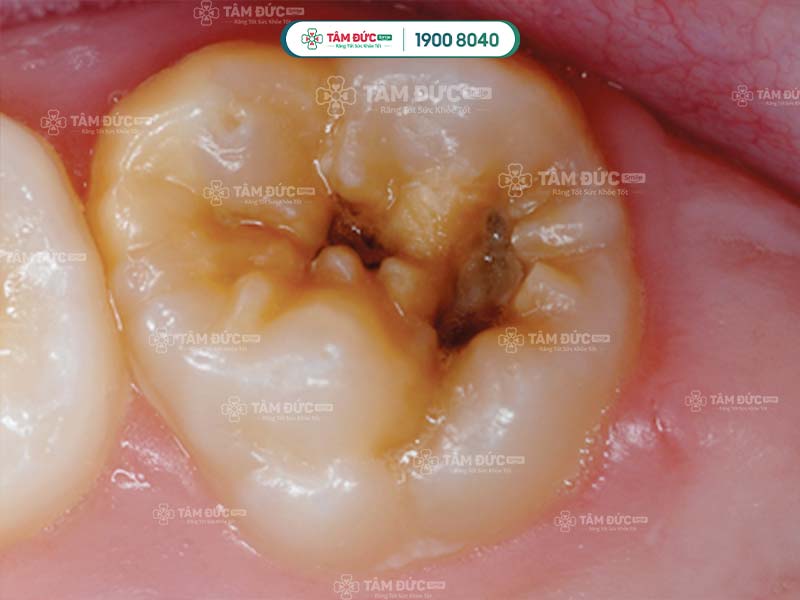

Trong nhiều trường hợp, răng sâu nặng hình thành ổ viêm tại các kẽ răng, việc lây lan sâu răng càng diễn ra nhanh chóng. Men răng bị mài mòn nhanh, thậm chí sâu răng có thể ăn vào tủy, làm hoại tử tuỷ và mất răng vĩnh viễn.

Nếu nhận thấy sâu răng đang tấn công, Quý khách hãy đến gặp bác sĩ để được điều trị ngay bây giờ. Ở giai đoạn đầu, sâu răng chưa gây đau nhức, nhưng Quý khách có thể thấy những đốm đen nhỏ trên răng.

Lúc này, bác sĩ sẽ cạo bỏ lớp răng bị hỏng và dùng vật liệu trám răng để trám bít lại trước khi sâu răng tiến triển nặng hơn.